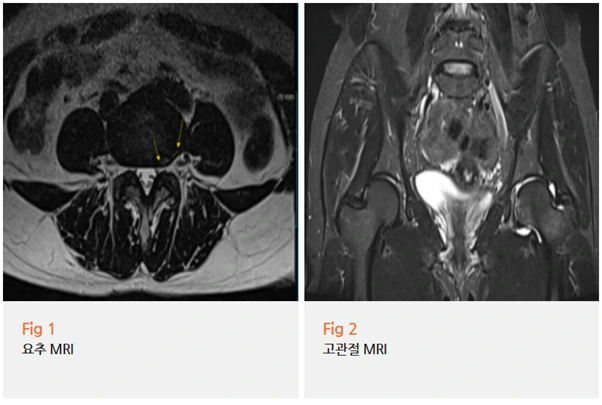

당일 요추 및 고관절 MRI 검사를 시행한 결과,

요추 4-5번의 추간판 질환과 함께

좌측 고관절 부위에서 염증 소견이 확인되었고,

고관절충돌증후군으로 진단되었습니다.